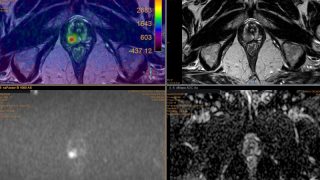

APT, una innovadora técnica de resonancia magnética que detecta tumores cerebrales sin contraste intravenoso

La imagen por transferencia de protones de amida, APT, es una técnica emergente dentro del campo de la resonancia magnética, RM, que está ganando cada vez más protagonismo, especialmente en el diagnóstico y seguimiento de tumores cerebrales. A diferencia de los métodos convencionales que requieren la administración de gadolinio u otros medios de contraste intravenosos, […]